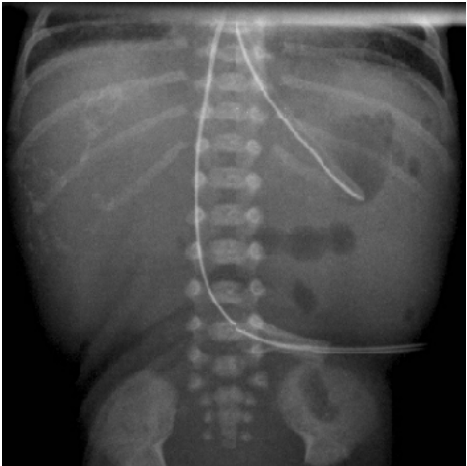

11 剛出生的新生兒被發現有腹脹,餵奶後有嘔吐,腹部 X 光如下圖,最可能是下列何種疾病?

(A) acute appendicitis (B) meconium peritonitis (C) pneumoperitonium (D) Meckel’s diverticulum